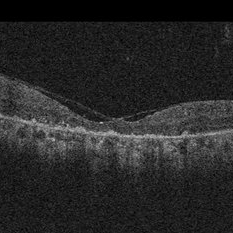

Ushers 2

Jun 29 2014 by John S. King, MD

Photographer: Wayne A Ladlee Jr

Condition/keywords: usher's syndrome